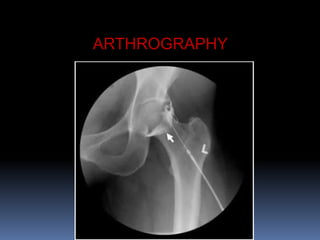

ARTHROGRAPHY

 Arthrogaphy is the study of

joint aftr the use of the gas

or cntrast medium into it.

 Through injection of the dye

or gas iinjury to cartilage or

ligaments can be visualized

 Arthrography can beusefull

in knee arthrogram.